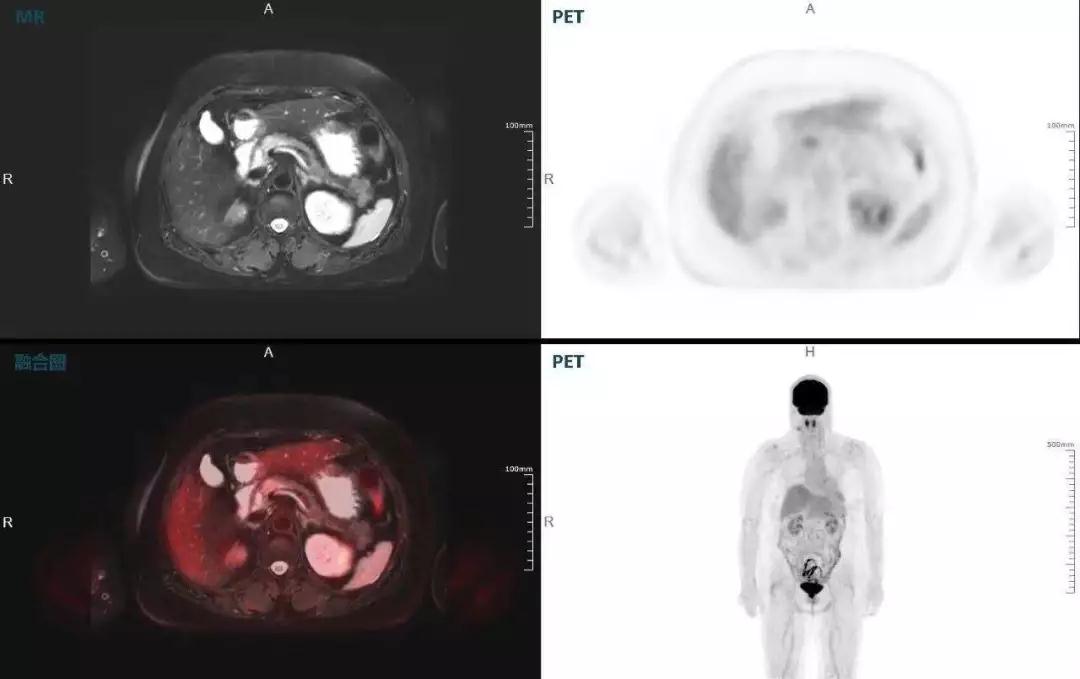

聯(lián)影“時(shí)空一體”超清TOF PET/MR搭載的壓縮感知技術(shù),能夠同時(shí)實(shí)現(xiàn)16期成像,精準(zhǔn)捕獲肝臟動(dòng)態(tài)影像的每一瞬間,同時(shí)兼顧早期與晚期等全部期相的完整病灶信息,實(shí)時(shí)、全方位鎖定病灶。同時(shí),基于其2.8mm超高分辨率,能夠精細(xì)呈現(xiàn)腫瘤邊界信息,捕捉局部微小病灶與遠(yuǎn)端轉(zhuǎn)移灶,助力醫(yī)生精準(zhǔn)診斷。

(對(duì)于同一例肝臟惡性腫瘤,PET-CT與PET/MR成像對(duì)比??梢钥吹?,聯(lián)影PET/MR圖像對(duì)腫瘤邊界和FDG高濃聚區(qū)域清晰顯示。)

胰腺癌

中山醫(yī)院核醫(yī)學(xué)科在臨床實(shí)踐中發(fā)現(xiàn),基于聯(lián)影“時(shí)空一體”超清TOF PET/MR,不僅解剖信息和代謝信息能夠完美融合呈現(xiàn),同時(shí)精細(xì)展示局部病灶與周圍組織的復(fù)雜關(guān)系,并能全盤檢測(cè)病灶的全身轉(zhuǎn)移,為醫(yī)生臨床診斷提供更豐富信息。

(胰腺腫瘤,MR顯示胰腺體部信號(hào)異常,PET顯示稍高攝取,結(jié)構(gòu)改變和功能異常提示胰腺M(fèi)T可能大。)